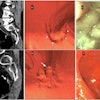

The report found that oncology imaging is combining with methods such as in vitro tissue analysis, biomarker tests, and cancer screening to bring real-time monitoring of tumors to the clinical setting to help avoid unnecessarily damaging tissues.

In addition, molecular imaging provides imaging methods for in vivo monitoring of cellular and molecular processes, and new contrast agents are expected to advance the efficacy of cancer imaging and detection.